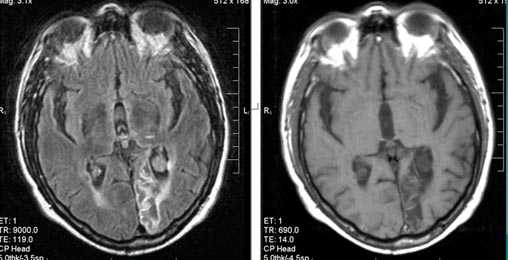

Внутримозговая гематома (граница острой и ранней подострой стадий - 3 суток), осложнившаяся внутрижелудочковым кровоизлиянием.

Внутримозговая гематома, поздний подострый период (14-21 день) с перифокальным отеком вокруг гематомы.

Внутримозговая гематома правой теменной доли. Граница поздней подострой и ранней хронической стадии. В Т2-ВИ виден ободок гемосидерина (стрелка).

Хочется подчеркнуть возможность МРТ в выявлении последствий геморрагического поражения - остается хорошо дифференцируемый по Т2 ободок гемосидерина, недоступный для визуализации при других методах нейровизуализации.

Стрелками показан ободок гемосидерина по периферии постишемической кисты.